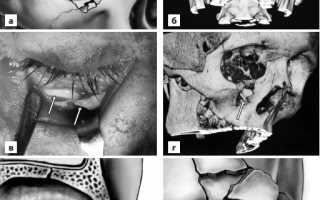

- Среднеэнергетический перелом характеризуется типичной для данной нозологической формы клиникой, умеренным смещением отломков; предполагает открытую репозицию и жесткую фиксацию костных фрагментов с использованием типичных доступов. Это самая обширная группа пациентов, требующая стандартных алгоритмов лечения (а-г — среднеэнергетический перелом нижнего края и нижней стенки глазницы).

- Наконец, высокоэнергетическая разновидность — редко возникающий мелкооскольчатый перелом с крайними степенями смещения и выраженной нестабильностью отломков, нарушением архитектоники лица (д — высокоэнергетический перелом трех стенок орбиты, е — крайняя степень высокоэнергетического перелома, обычно являющегося составной частью панфациальной травмы. Мелкооскольчатый перелом всех стенок глазницы нередко сочетается с разрушением глазного яблока).

Для полноценной визуализации и репозиции поврежденных костных структур требуются многочисленные доступы, а тяжесть травмы предполагает индивидуальную хирургическую тактику в каждом конкретном случае.